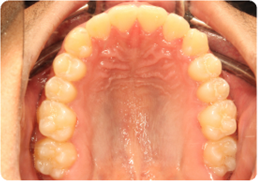

Each case shows the front view and an arch or side view, before and after BioLign Method-guided treatment.

All cases treated within 6–12 months.

Overlapping front teeth aligned with arch form correction